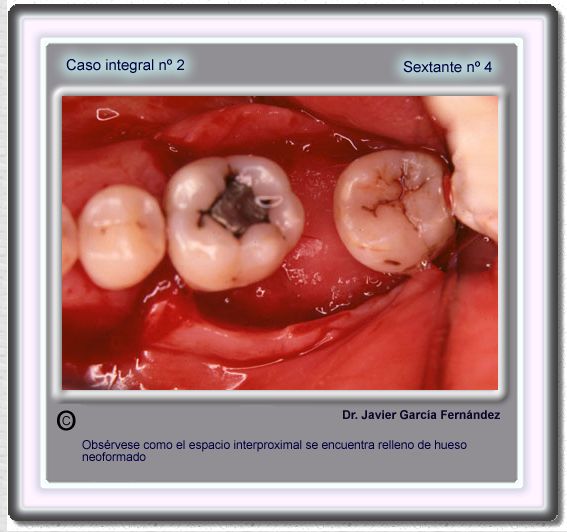

image 66